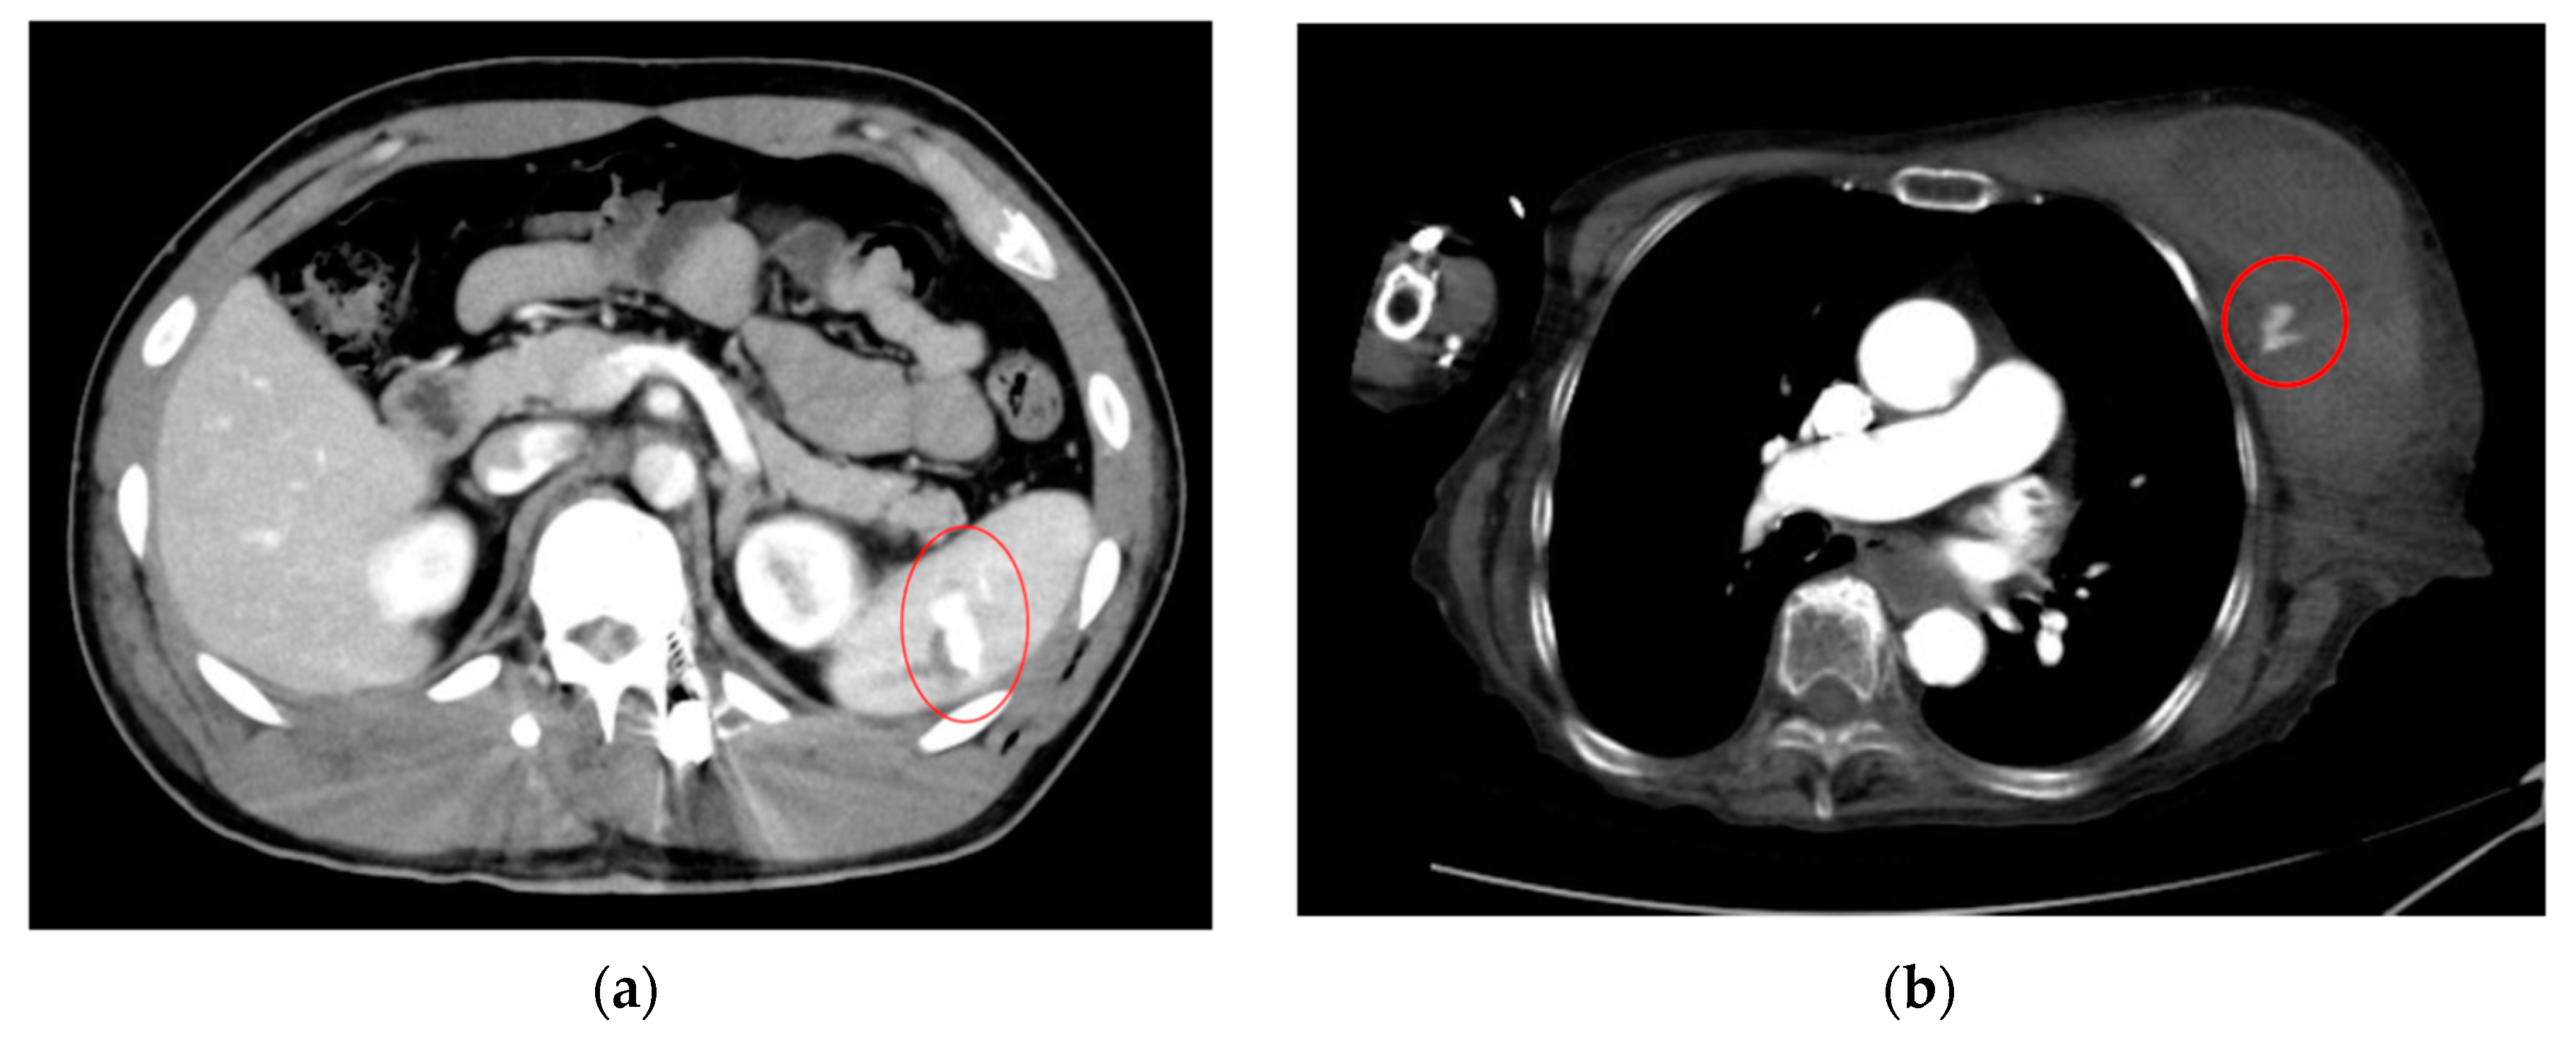

As an example, Figure 1 shows extravasation-induced hemorrhage from a polycystic kidney. Identifying the precise bleeding site on the computed tomography (CT) image presented a challenge. However, upon reviewing the angiography findings, it became evident that the bleeding originated from the area depicted in the CT image. In Figure 2, two instances of extravasation-induced hemorrhage are depicted, marked with the circles. Firstly, (a) displays a pseudoaneurysm visible post-spleen injury. Secondly, (b) illustrates a muscle hematoma in the chest region. In Figure 3, two cases of extravasation-induced hemorrhage are evident. In (a), circles mark extravasation on a fractured pelvic region, indicating a significant injury. Meanwhile, (b) showcases an intragluteal hematoma, highlighting the varied presentations of extravasation across different anatomical contexts. These CT images provide valuable insights into the varied presentations of extravasation cases across different anatomical contexts.

Figure 2.

Extravasation-induced hemorrhage shown with circles: pseudoaneurysm after spleen injury (a), and (b) muscle hematoma in chest.